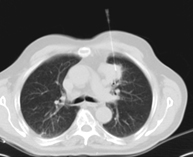

- High resolution Chest CT

Diagnostic test to examine the lung using CT (Computed Tomography) equipment to obtain two- and three-dimensional images, that allow a highly specific anatomical examination of the lung, being able to assess very small anatomical structures. This technique is very important among patients with suspected lung disease.